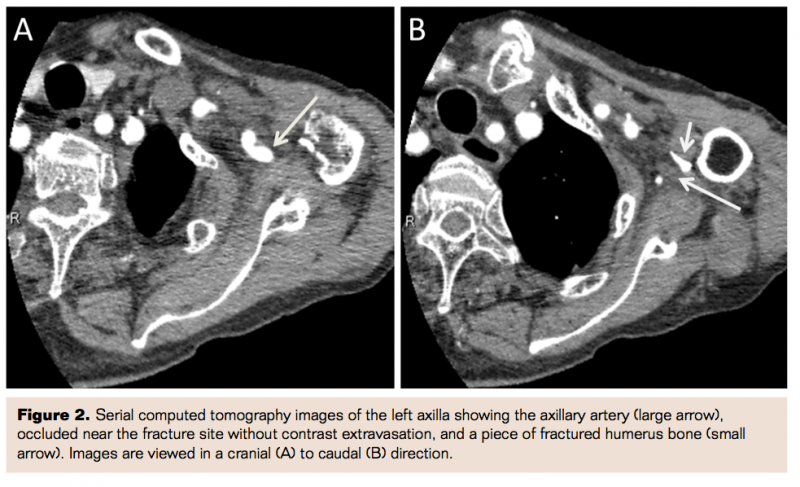

An 82-year-old Japanese male presented with severe pain in the left shoulder and arm, with discoloration of hand and fingers, 2 hours after falling at home. His medical history included osteoporosis and prostate cancer that were well controlled with medical treatment. On admission, his vital signs were stable. On physical examination performed approximately 2 hours after the fall there were no brachial, radial, or ulnar pulses in the left arm. There were no open wounds. The hand and forearm were pale and cool, but the skin of the fingers was dark, indicating critical ischemia. In spite of mild hypoesthesia, there was no weakness in his hand and fingers. His hemoglobin was 9.6 g/dL and the estimated glomerular filtration rate was 71.9 mL/min/1.73 m2. The serum creatine kinase level was 123 IU/L. An initial radiography of the left shoulder revealed a three-part fracture of the left proximal humerus with severe medial displacement, according to Neer classification. To restore blood flow, he underwent immediate closed reduction under interscalene brachial plexus block (Figure 1). However, the distal pulses were still not palpable and the fingers remained dusky. An early phase contrasted computed tomography (CT) scan showed an abrupt obstruction of the left axillary artery adjacent to the fracture site, without evidence of contrast extravasation. This finding suggested occlusion associated with an intimal tear caused by the displaced shaft of the humerus rather than arterial transection. Late-phase contrasted CT images revealed a faint visualization of the brachial artery distal to the occluded axillary artery (Figures 2 and 3). His upper limb was thought to be salvageable because of the lack of weakness in his left hand and fingers.